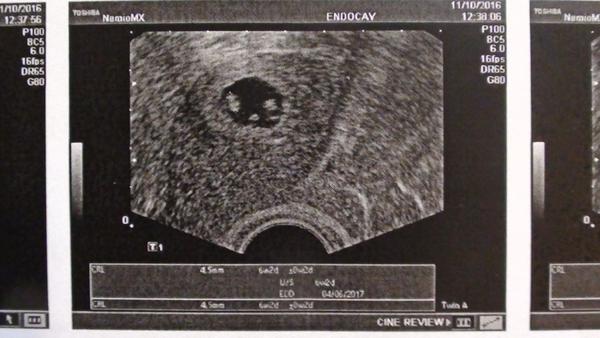

Dneska jsem byla na dalším UTZ, hodnota pátečního HCG stoupla na 40757 a na UTZ dva základy plodů, oba se srdeční akcí

@itworks jojo jednovajecna, zavedeno jedno embryjko, 5ti denni hatchujici blastocysta